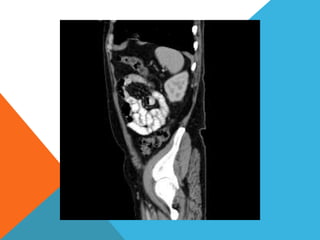

El paciente presentó síntomas de sangrado digestivo y pérdida de peso. Exámenes revelaron gastritis crónica asociada a H. pylori. Un tumor fue descubierto en una colonoscopia normal. La cirugía removió un tumor fibroide solitario, una rara neoplasia mesenquimal que usualmente crece lento y tiene bajo potencial de malignidad. El pronóstico después de la remoción quirúrgica es generalmente bueno.